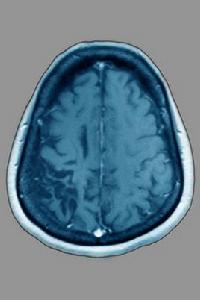

腦萎縮的易患人群

腦髓空虛是腦萎縮的基本病理變化,腎氣腎精虧虛是其基本病機。大量的實驗和臨床研究表明,老年腎虛者大多腦功能下降,大腦神經細胞減少,遞質含量及遞質受體數量均下降,內分泌功能紊亂,免疫功能下降,自身免疫和變態反應增加,體內自由基的容量及過氧化物隨年齡增加而積累,而抗自由基損傷的物質如SOD含量下降。這些變化說明腎虛是老年性痴呆的重要病因。以腎虛為主要病機,以補腎填精益髓為治療大法組方遣藥,來延緩衰老,防治老年性痴呆,可以說是傳統共識。但不管病情如何變化,腎虛始終貫穿老年性痴呆的整個病程,是其最本質的特徵。臨床只要以補腎填精益髓立方防治老年性痴呆,就能取得較好療效。腎虛是老年性痴呆發病的重要病理基礎,痰凝血瘀是老年性痴呆發病的重要因素。痰瘀既是病理產物又是致病因素,痰凝血瘀推動了老年性痴呆的發生髮展。正常衰老過程本身就有血瘀證存在的潛在性。故瘀血內停也是痴呆發病的重要原因,瘀阻心腦則可心神不安,心悸失眠,健忘痴呆,神昏譫語。《血證論·瘀血》也說:“瘀血攻心,心痛、頭暈、神氣昏迷……。”腦萎縮老年性痴呆所表現出的呆板、遲鈍、寡言、傻哭傻笑、舌質暗淡或舌質淡、苔白膩等各種臨床症狀正屬於中醫痰凝血瘀範疇。 住了這一病機,也就抓住了老年性痴呆的本質和發展的一般規律,臨床治療就可以取得較好的療效。以補腎活血化痰立方,防治老年性痴呆則可做到標本兼顧,是一種行之有效方法。提高記憶力、解決腦痴呆、對抗衰老,國家唯一純中藥治療痴呆症首選藥物。 綜上所述,腎虛是老年性痴呆的主要原因和基礎,痰凝血瘀是發病的直接原因。腎虛為本,痰凝血瘀為標,本虛標實正是老年性痴呆的基本病機。正虛可以生痰生瘀,痰瘀又可加重正虛,二者互為因果,導致了病情的發生髮展。

神經靶向修復療法使神經生長因子通過靶向方式作用於病灶。激活處於休眠狀態的神經細胞,實現神經細胞的自我分化和更新,恢復神經遞質的傳導功能,重建神經環路,增加腦部供氧和血液循環。